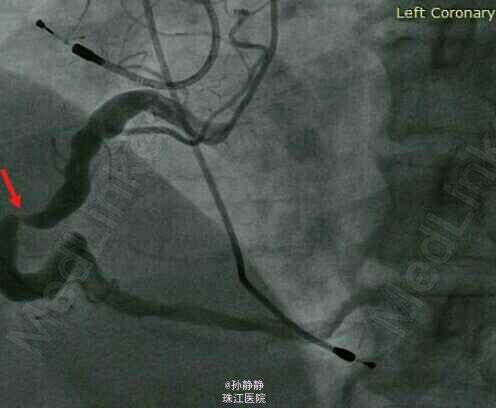

查体:血压144/85mmHg,心率80次/分,心律绝对不齐,心界不大,未闻及杂音。颈部、腹部、腰背部未及异常搏动或血管杂音。 辅助检查 :红细胞沉降率(ESR)11mm/h,高敏C反应蛋白(hs-CRP)7.73mg/L,谷丙转氨酶(ALT)36IU/L,谷草转氨酶(AST)23IU/L,肌酸激酶(CK)44IU/L,肌酐(Cr)104.59μmol/L,K+4.14mmol/L,肌酸激酶同工酶(CK-MB)2.913ng/ml,肌红蛋白(Myo)20.78ng/ml,心肌肌钙蛋白I(cTnI)0.125ng/ml,氨基末端脑钠肽前体(NT-proBNP)414pg/ml。 心电图示房颤。 超声心动图示左房前后径4.2cm,左室舒张末径4.9cm,左室射血分数63%,室壁厚度正常,运动协调,收缩幅度正常。冠脉造影示第一对角支狭窄95%,右冠脉中段狭窄95%。

诊断:1.冠心病2.心绞痛3.冠脉扩张 处理:PCI。术后次日晨查CK-MB4.82ng/ml,Myo36.84ng/ml,cTnI0.084ng/ml,冠脉造影显示右冠中段狭窄解除。